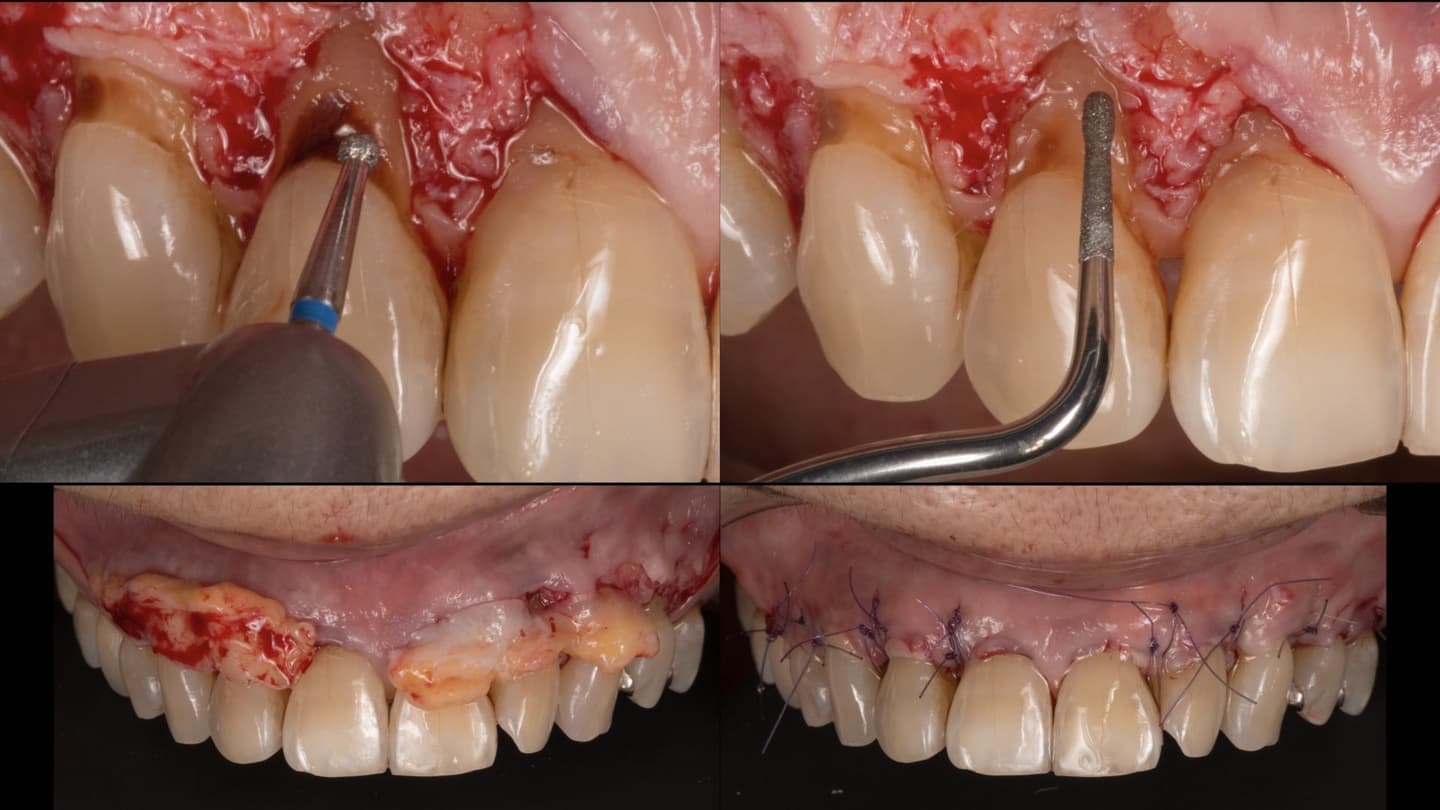

一般的な歯周病(慢性歯周炎)に関する治療法は、ほぼ確立されています。私達は、出来る限り歯を抜かずに歯周病治療する事で歯を温存できるよう日々努力しています。

適切な治療を行えば、健康な口腔内を実現できます

歯周組織再生を基礎研究から生涯のテーマとして取り組んできました